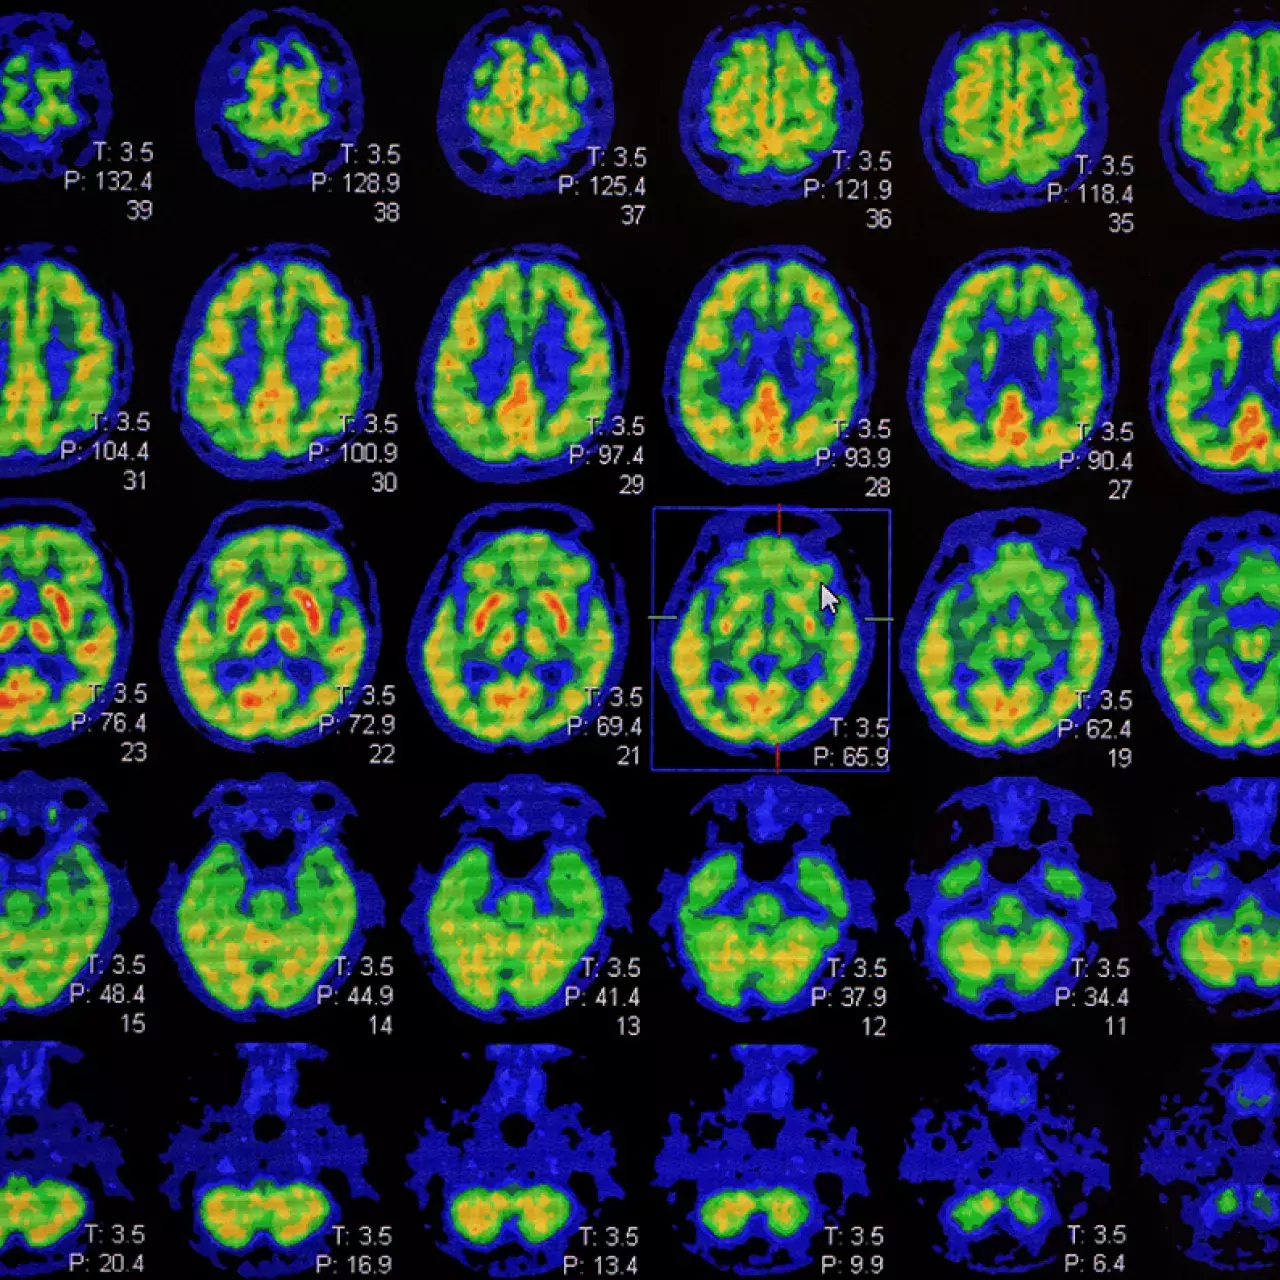

Troubles cognitifs

Un consensus européen pour un diagnostic individualisé de la maladie d’Alzheimer

Maladie d'Alzheimer

Conférence internationale sur les futures cliniques de la mémoire